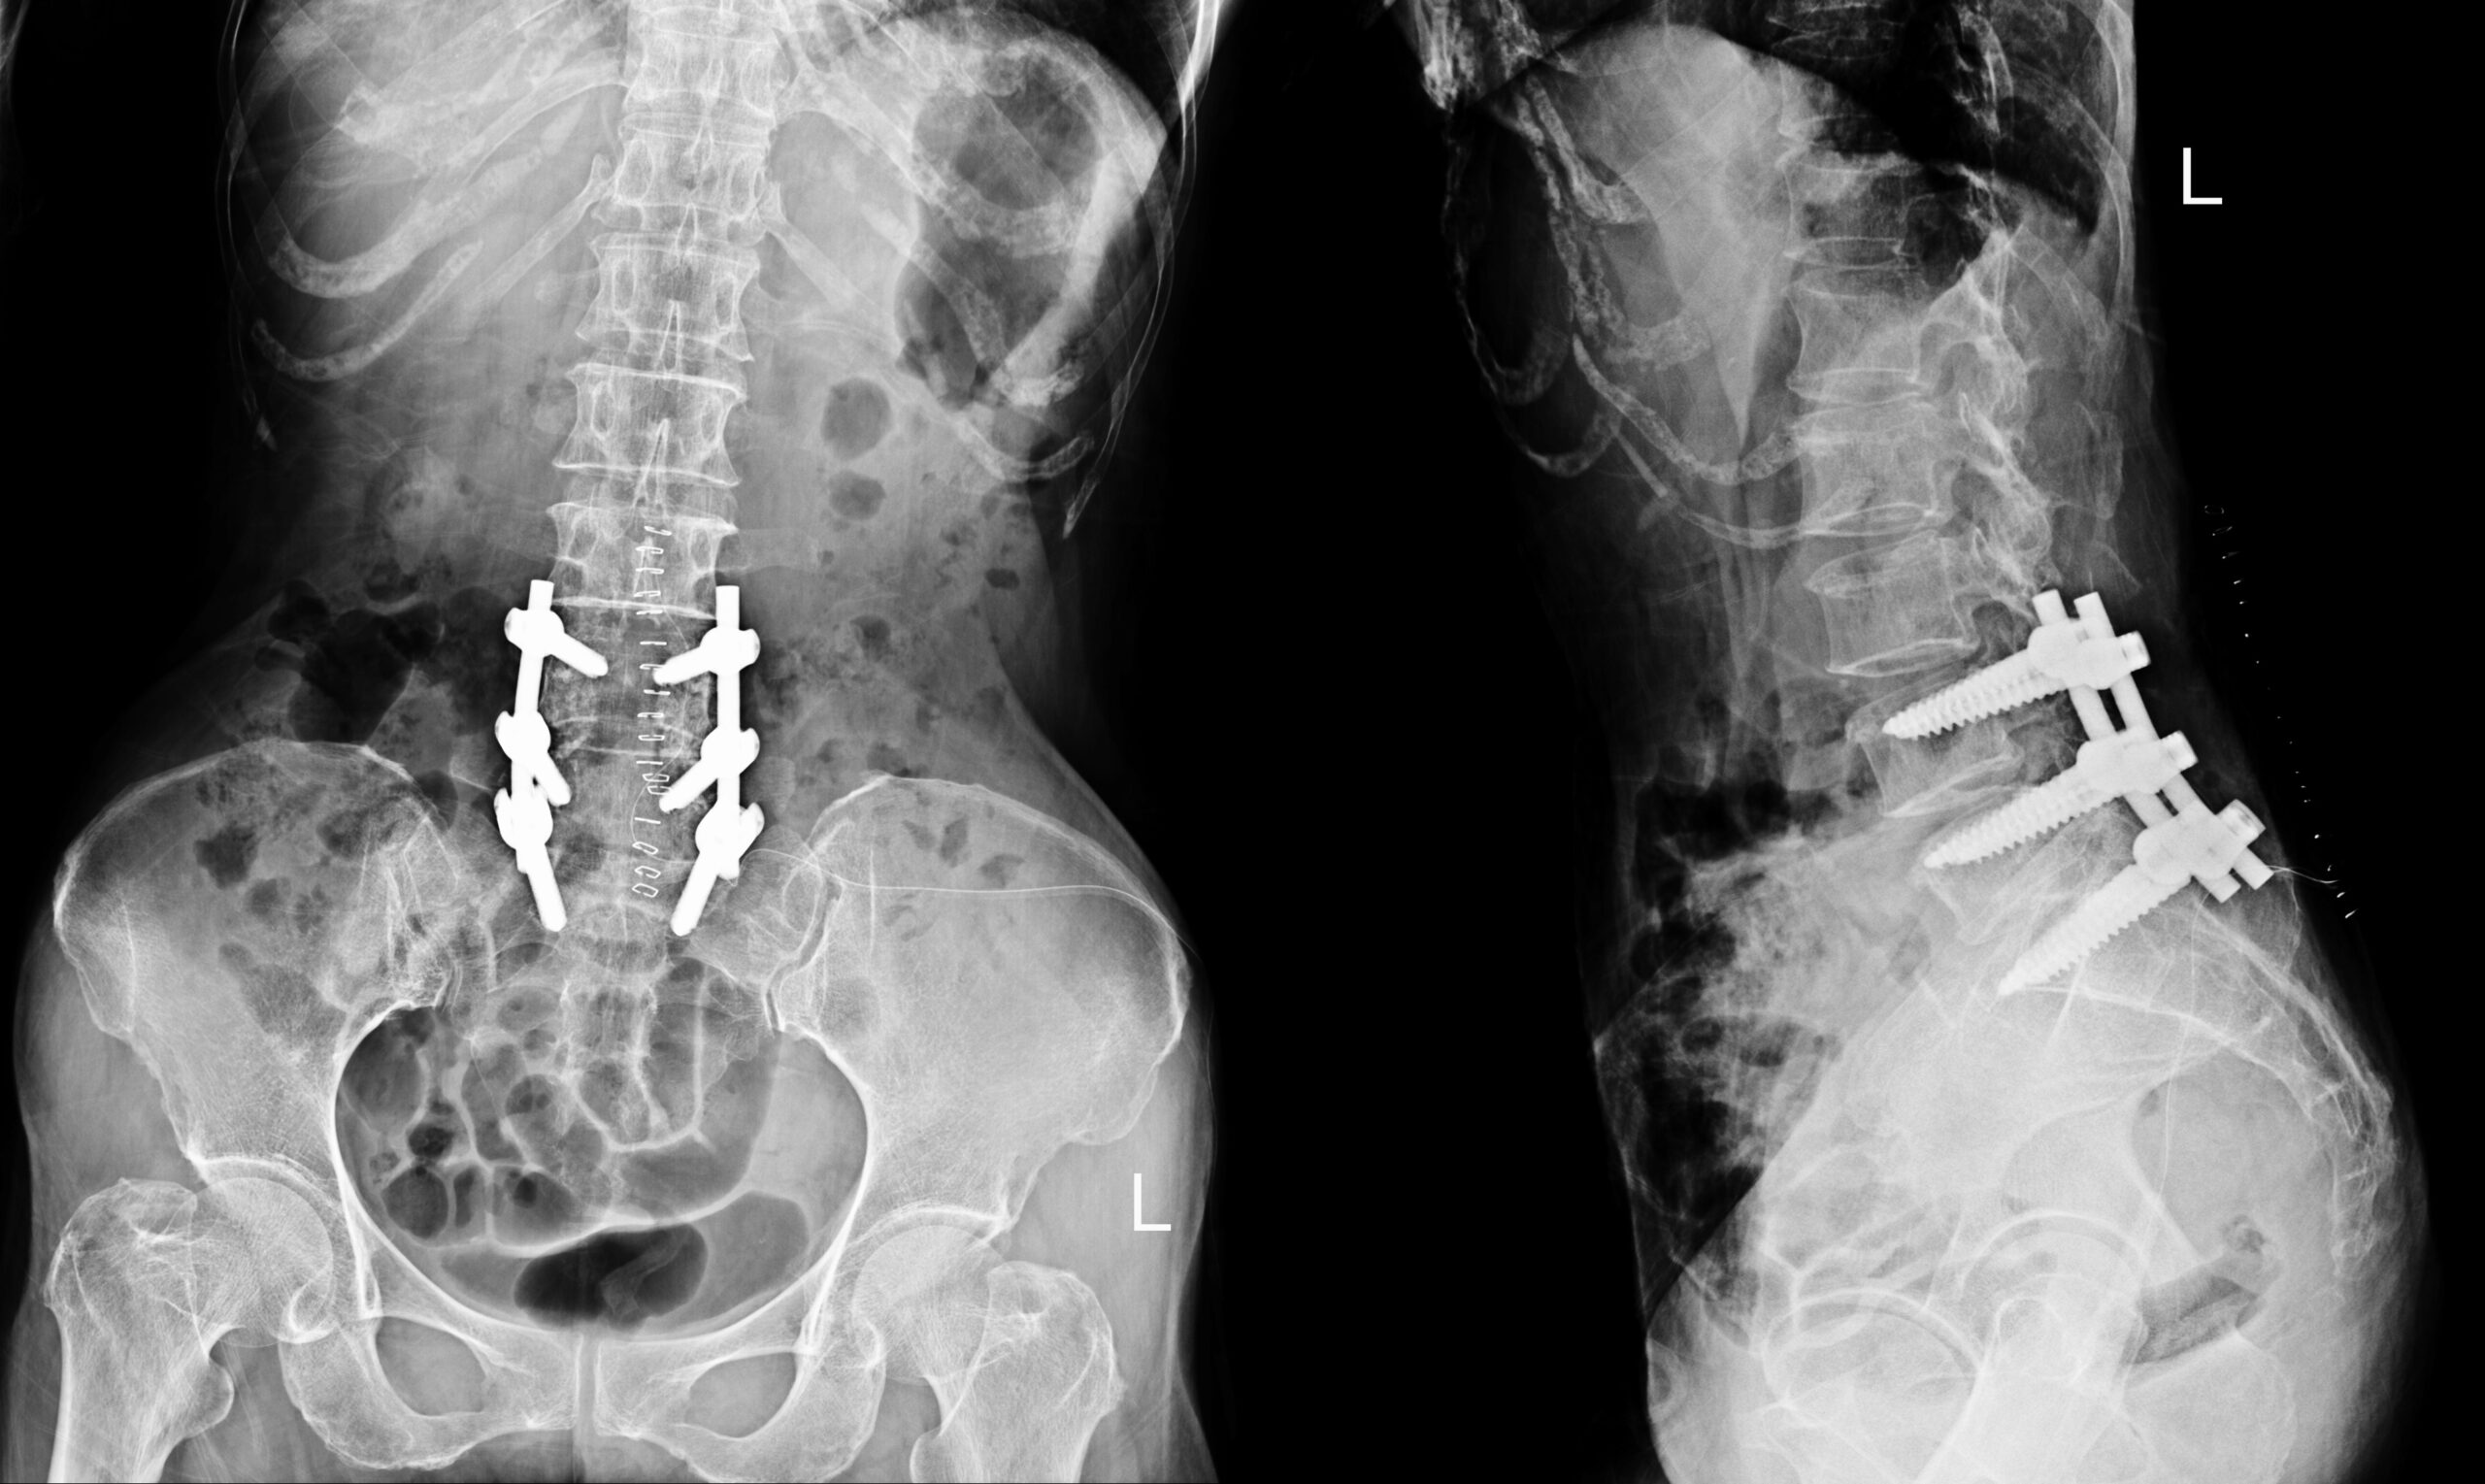

Patients diagnosed with lumbar spondylolysis and spondylolisthesis are sometimes referred to surgery. The main surgical procedures is spinal fusion, This surgery is designed to stabilize the spine and provide decompression to relieve pressure on the nerves.

In spinal fusion, two vertebrae are joined together, frequently using instrumentation (rods and screws) and bone grafts; in decompression, the bone or tissue that is compressing nerves is removed.